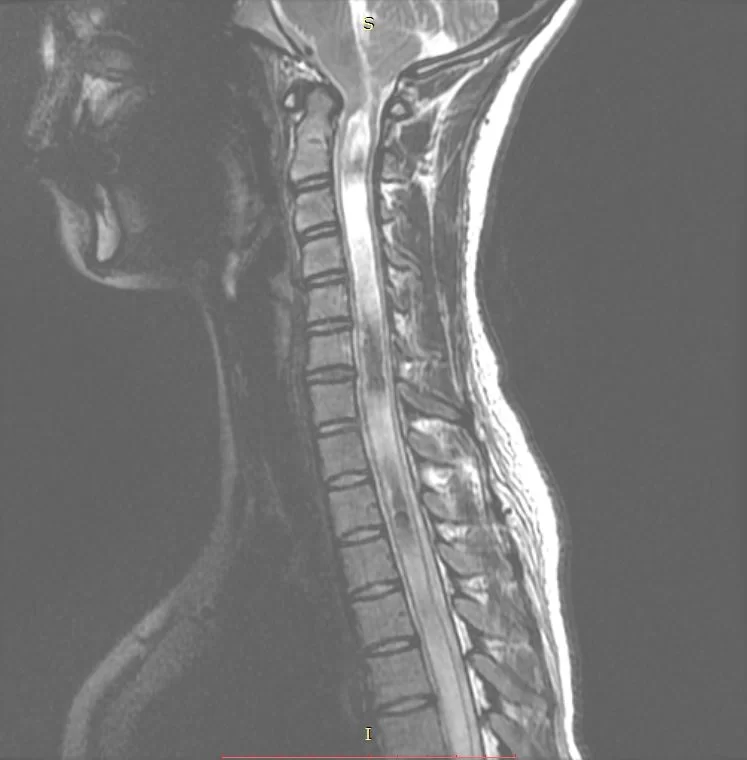

Σύνδρομο Chiari – Συριγγομυελία

Νεαρή ασθενής 17 ετών με εκτεταμένη συριγγομυελία από την αυχενοπρομηκική συμβολή έως το τελικό τμήμα του νωτιαίου μυελού, λόγω συνδρόμου Chiari. Κλινικά αιμωδίες (μουδιάσματα) άνω